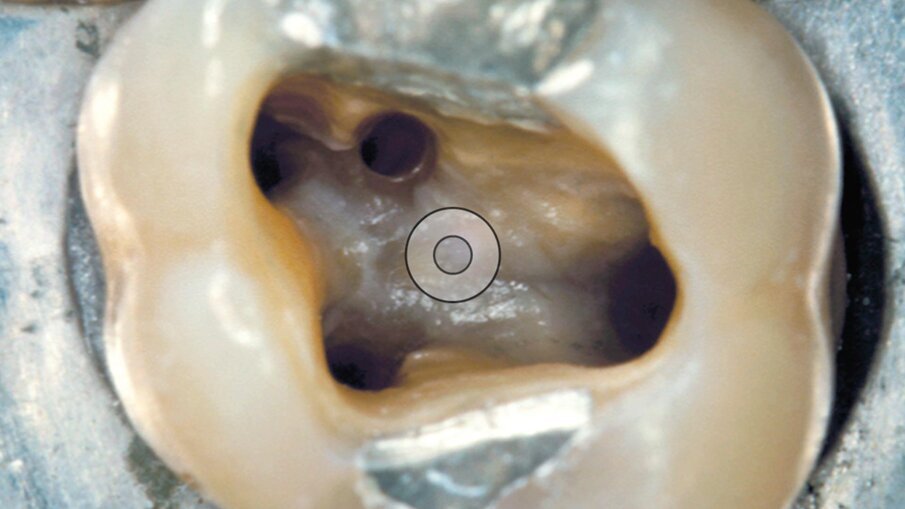

A-C TIP ED52: reperimento del canale mesio-palatino (MB2) (Fig. 7)

Il primo molare superiore deve essere considerato, in base agli ultimi lavori scientifici, un dente con 4 canali (Fig. 8). L’utilizzo della A-C Tip ED52 ci permette contemporaneamente di eliminare la sporgenza di dentina e parte dell’iniziale brusca curvatura coronale. L’imbocco del MB2 viene così trasferito sul pavimento della camera pulpare, consentendo un accesso rettilineo al canale. Questo permette di vedere chiaramente l’imbocco del canale e poterlo poi sondare senza problematiche interferenze coronali.

La A-C Tip ED52 ha forma troncoconica. La parte lavorante è lunga 8 mm, la punta ha un diametro di 1 mm, il diametro massimo dell’inserto alla fine della parte lavorante è di 1,54 mm. La punta dell’inserto è attiva.

La punta A-C Tip ED52 può essere utilizzata sino a circa l’80-90 % della massima potenza raggiungibile con le sorgenti di ultrasuoni dedicate all’endodonzia oggi disponibili sul mercato.

Fig. 7 - La A-C Tip ED52 è disegnata per facilitare il reperimento e il sondaggio del canale MB2.

Fig. 8 - I quattro canali di questo primo molare superiore sono stati detersi e sagomati.